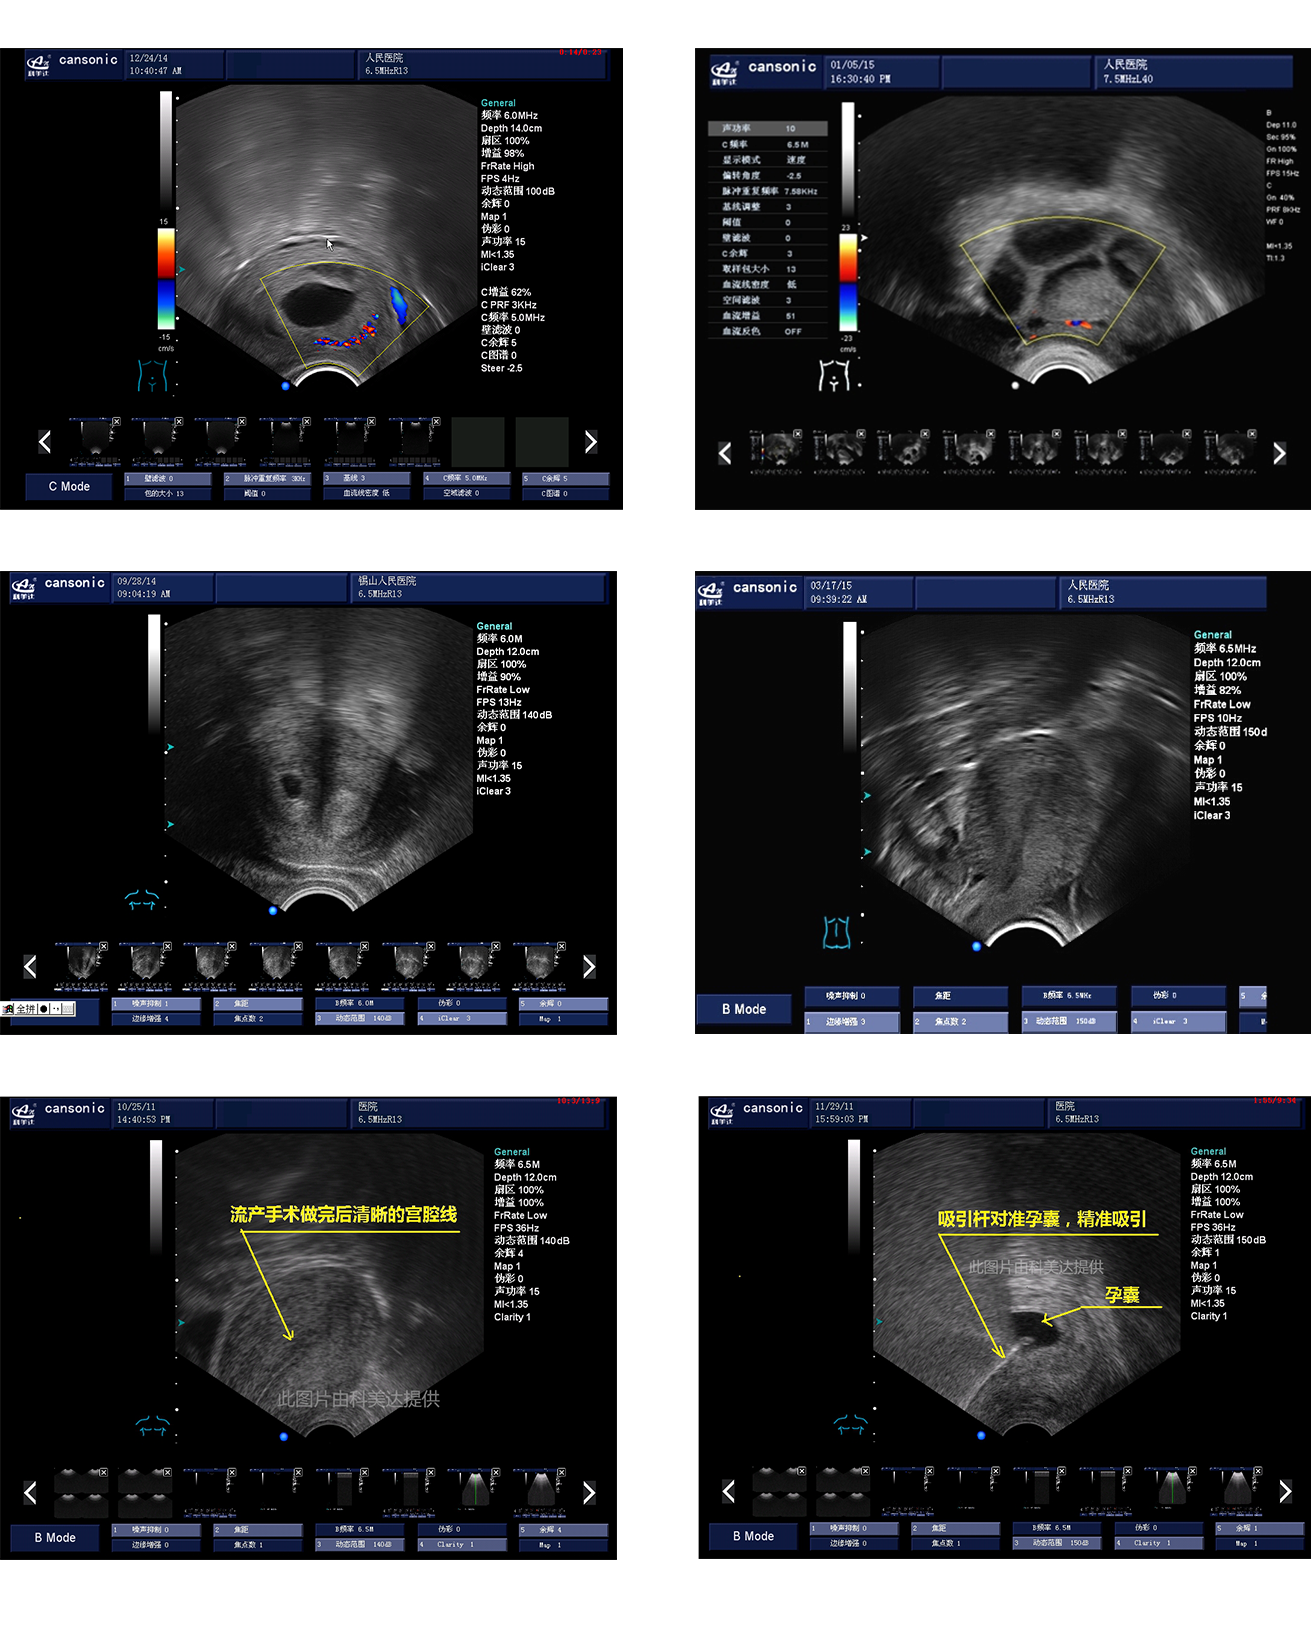

臨床圖示

1、融合業(yè)內(nèi)高端的硬件工藝及智能后處理算法,結(jié)合規(guī)范的操作流程,實現(xiàn)對宮腔手術(shù)的全程監(jiān)測

2、精準(zhǔn)數(shù)字濾波技術(shù),有效降低多普勒噪聲及運動偽像,提升血流及多普勒超聲圖像

4、能量多普勒POWER成像模式彩色多普勒Color成像模式

5、血流靈敏度高,清晰可見